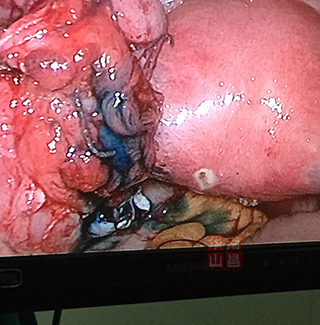

输卵管积水造口整形术后伞端可见美兰液流出